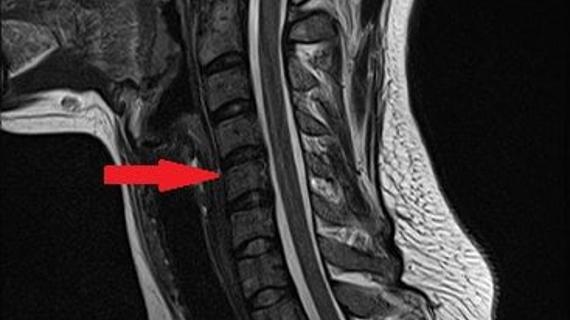

Рентген при остеохондрозе — это классический метод диагностики дистрофических изменений в хрящевой ткани. Обследование дает возможность исследовать нанесенный...